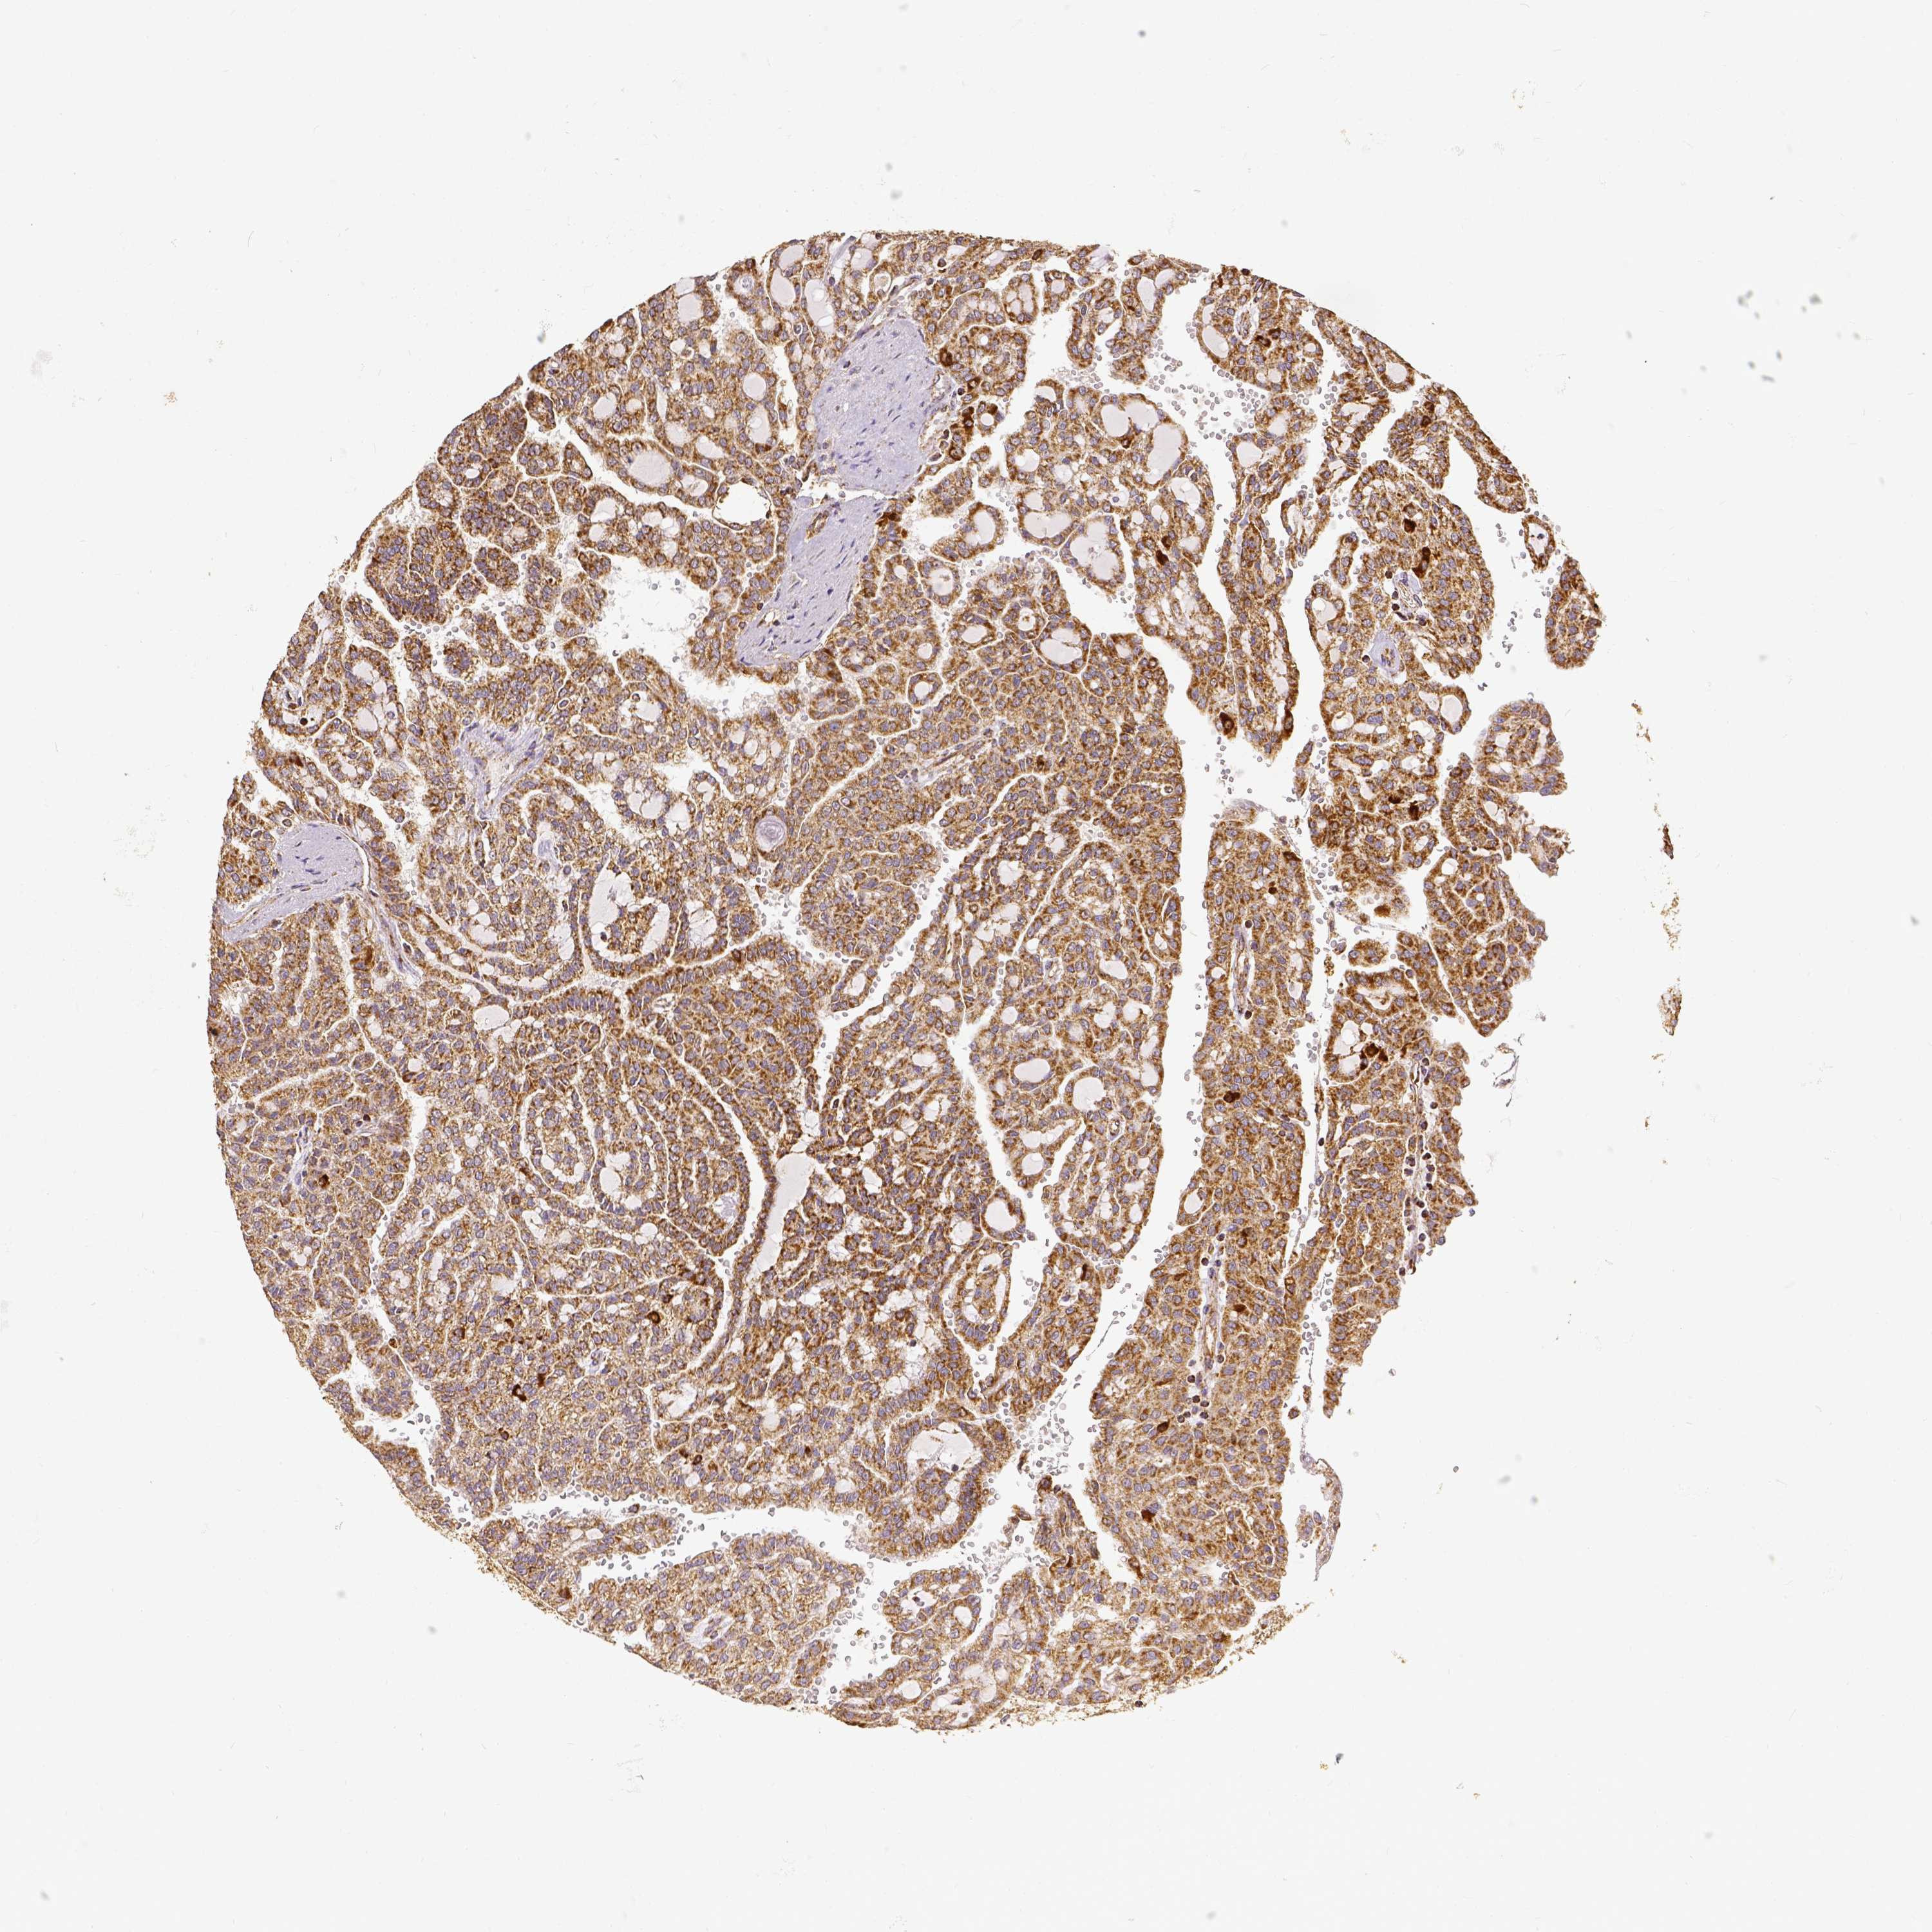

TCGA RNA samplesi

RNA-seq data is reported as average FPKM (number Fragments Per Kilobase of exon per Million reads), generated by the The Cancer Genome Atlas (TCGA) .

Normal distribution across the dataset is visualized with box plots, shown as median and 25th and 75th percentiles. Points are displayed as outliers if they are above or below 1.5 times the interquartile range. FPKM values of the individual samples are presented next to the box plot.

Average pTPM 109.1